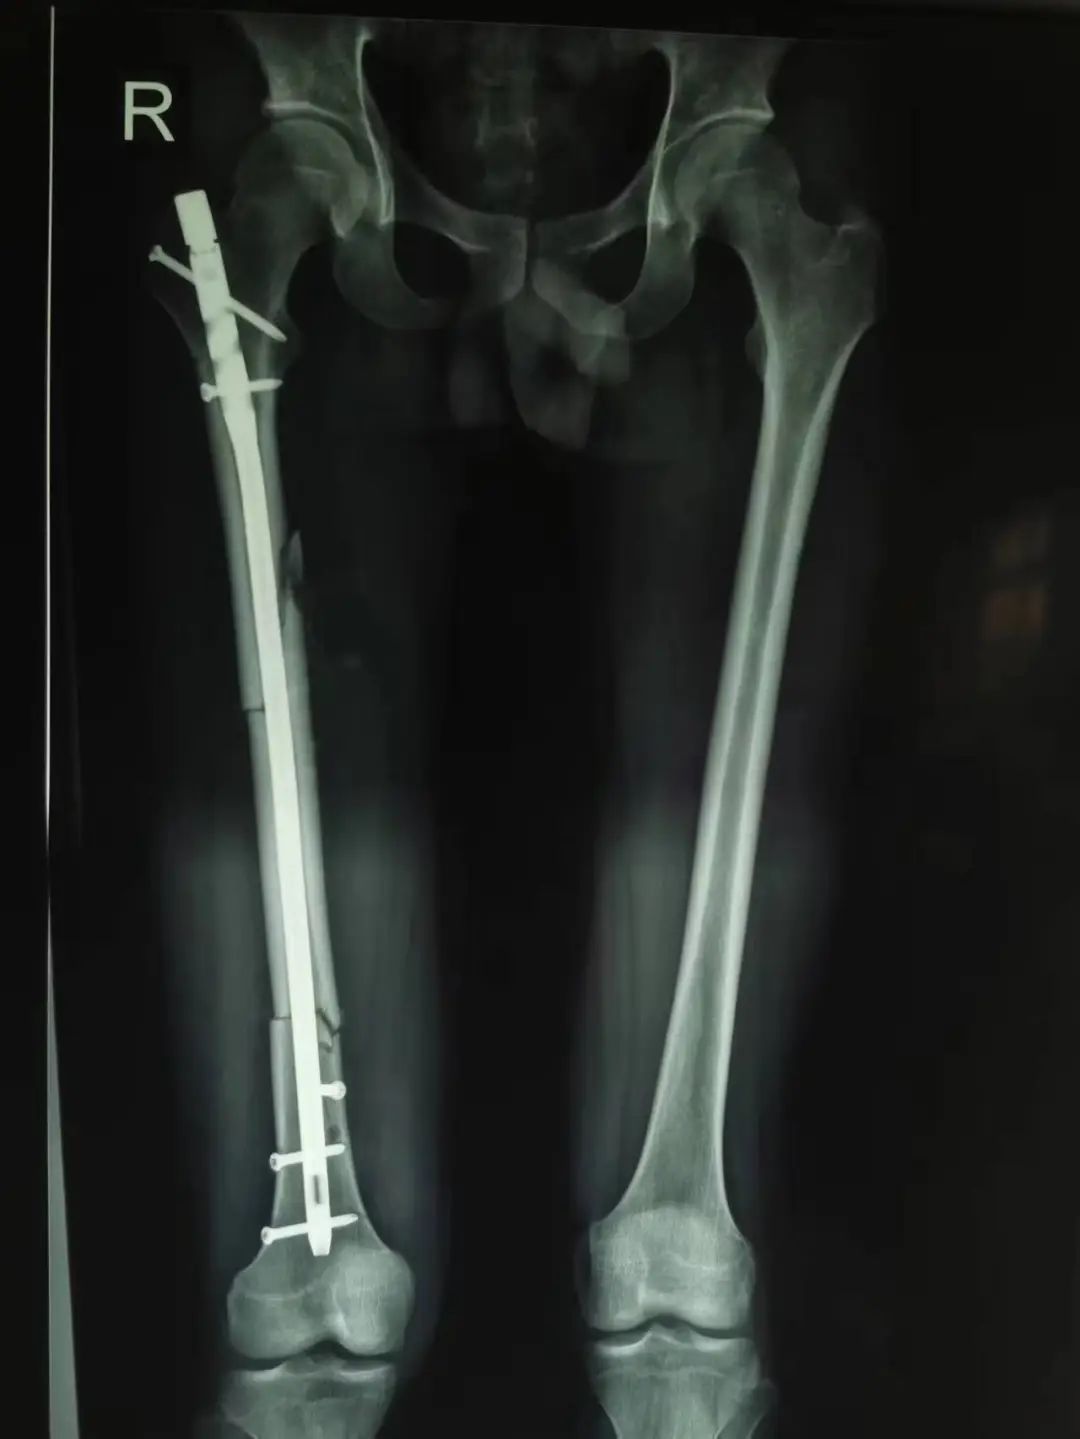

入院后,结合相关检查,为患者行「右股骨干骨折切开复位内固定、同种异体骨植骨术」,术中通过 x 线透视复查,见骨折复位恢复正常。通过院前院内的共同努力,在急诊外科未智慧主任、陈伟医生和护理人员的精心照护下,患者已经能够掌握一些康复功能锻炼,并于 10 月 26 日康复出院。